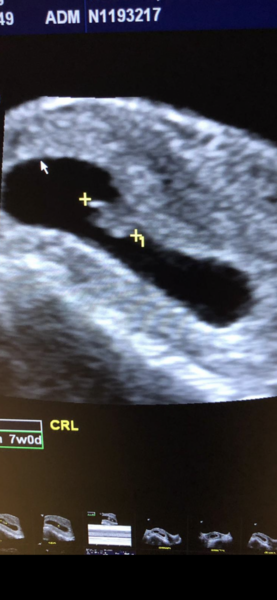

@Xx40yearsyoungxx aw thank you so much for thinking of me. We are delighted everything went perfectly at the scan and there was a super strong heartbeat 😊 everything crossed for you today as well x

@Sydgal22 glad your scan went well! Cute little bean! Did the measurements match up to where you thought you were? was it a tummy scan? Good luck to anyone else having their scan soon X

Sydgal22 · 11/07/2020 10:29

@Cocoblue22 yep measurements were spot on 7 weeks so due feb 27th! Ye it was a tummy scan, I had drank so much water as had to have a full bladder and they were 20 minutes late so I almost burst! She said didn’t have to be all full next time 😂😂

@Sydgal22 aww that's excellent then! Well done for not peeing haha I remember that from last time and they push down quite hard with the scanner don't they I remember literally running to the loo straight after with DS! It's great your measurements were spot on too! Exciting! Did you actually hear the heartbeat then? I wasn't sure if 7weeks was too early to hear it x

Sydgal22 · 11/07/2020 10:51

@Cocoblue22 I actually had to let a little out before I went in cause I was in full pain 😂

Nah you cant hear the heart beat this early but you can see it flicker on the screen and she takes a measurement of it, was 173 bpm which she said was super strong. I nearly want to tell people now ha but know I should try and wait! Are you having a scan?

Xx40yearsyoungxx · 11/07/2020 12:06

@Sydgal22 in car park having just had a scan and in shock - despite ZERO Symptoms - not one - and clear blue not going up to 3+ until way way late over 6 weeks I saw my little bean . I’m 6w5d . They went straight for an internal scan ( I though it was going to be a normal US) . Heart beat was 122 ( not sure if that’s good or bad ?)

Due 1st March 2020